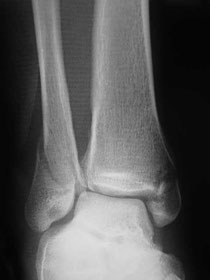

足関節果部骨折とは?

足関節果部骨折は、非常に多い骨折です。

原因として、転倒、転落、交通事故などにより、足首に強い外力が加わり生じます。

骨折に伴い、足関節周囲の靭帯損傷も生じます。

負傷時の外力の加わる方向により、骨折と靭帯損傷の組み合わせにより分類されます。

足関節とは、脛骨、腓骨、距骨による骨の構成を周囲に複数の靭帯で保護・安定されています。

診断

受傷起因、関節部の腫れ、圧痛などの確認後、レントゲン、CT画像診断を行います。